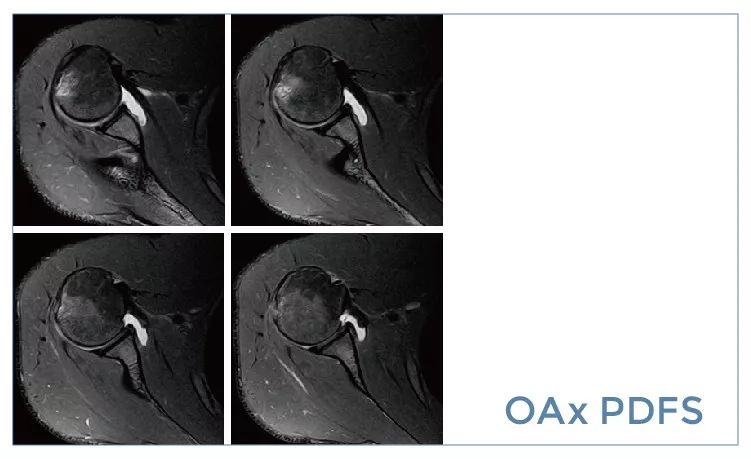

【朗润影像档案】磁共振影像病例分享(编号20190927)